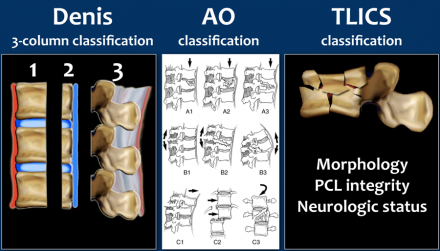

Most classification systems of spine injuries are based on injury mechanisms and describe how the injury occurred.

A problem with classifications such as the AO-classification is that they are usually complex, leading to high inter-reader variability.

Using the popular Denis three-column classification may lead to another situation since it uses the terms stable and unstable. In many cases, however, there is no good correlation with the necessity for surgery.

Furthermore, the word stability itself is ambiguous and may refer to direct osseous stability; it may refer to neurological stability and finally, to long-term (ligamentous) stability.

Both of these commonly used systems fail to systematically take into account the neurological status of the patient and the indication for MRI to determine the integrity of the posterior ligamentous complex.

For these reasons the Spine Trauma Study Group introduced in 2005 the Thoracolumbar Injury Classification and Severity Scale (1), with intention to be a reliable, ease-to-use tool to facilitate clinical decision making and as a practical alternative to cumbersome classification systems already in use.

The TLICS consists of three independent parameters:

- Injury Morphology

- Integrity of the Posterior Ligamentous Complex

- Neurologic status.

A parameter can be scored 0-4 points and the total score is the sum of these parameters with a maximum of 10 points.

The total score predicts the need for surgery as is shown in the TLICS algorithm. A total of more than 4 points indicates surgical treatment.